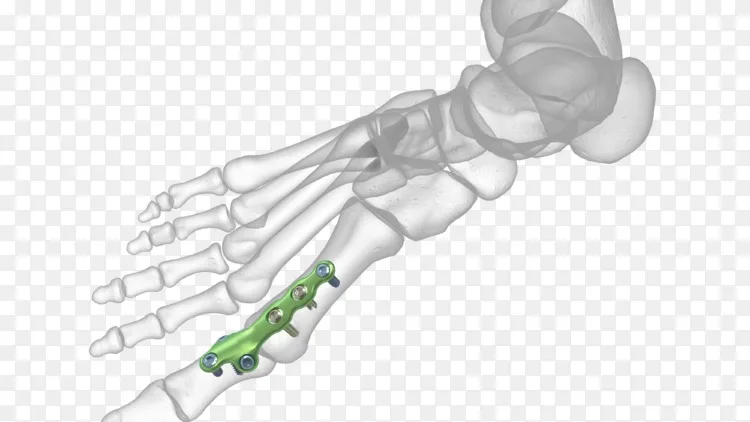

跖趾关节关节固定板 Mtp Carbofix Orthopedics 未锁定 锁定 金属

第一跖趾关节融合锁定接骨板 广州福娜瑞贸易有限公司

跖趾关节关节固定板 Dynaforce Mpj Crossroads Extremity Systems 金属